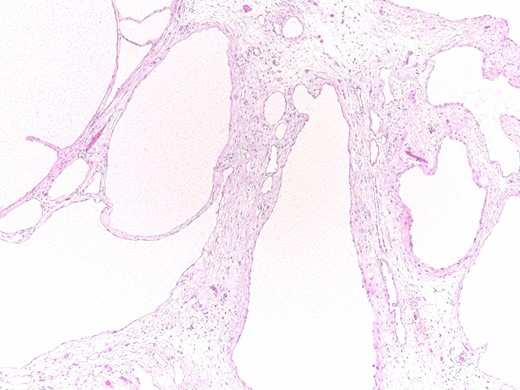

On gross examination a soft, yellowish tissue specimen was seen, measuring about 13 × 9 × 4 cm, composed of multiple cysts, up to 1 cm in diameter, containing a clear fluid. It was fixed in 10% formalin, embedded in paraffin, and the sections were evaluated by hematoxylin and eosin stain. Histologically, it consisted of cysts lined by a single layer of flattened to cuboidal mesothelial cells without atypia. Immunohistochemistry using an automated stainer (Ventana, Tucson, AZ) was performed and all tumor cells showed immunoreactivity for WT1 and Calretinin. Based on these findings, the final histological diagnosis was multicystic benign mesothelioma.

Histopathology results: cysts lined by flattened/cuboidal mesothelial cells.

Microscopically, the cysts of BMPM are lined by cuboidal or flattened mesothelial cells. In the latter case, BMPM could simulate the appearance of a cystic lymphangioma, but the former exhibits mesothelial markers, such as calretinin and WT1. Ross et al. [10] believe that BMPM is probably the result of a peritoneal reactive proliferation, forming multiple peritoneal inclusion cysts, and not a true neoplasm. The natural history of this disorder, with its great tendency to local recurrence and its tumor-like appearance, suggests its neoplastic pathogenesis, but both of the hypothesis can be argued.